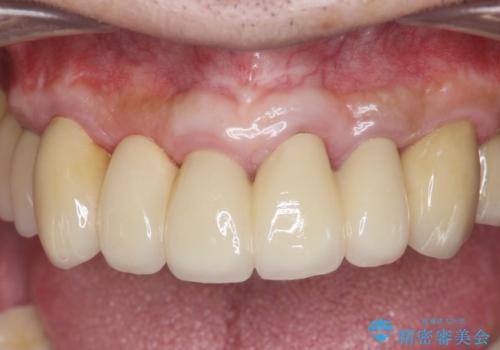

歯周病治療を伴う前歯審美セラミック治療

歯周外科を行ったことで非常に安定した歯周環境となり、引き締まった歯ぐきとなりました。